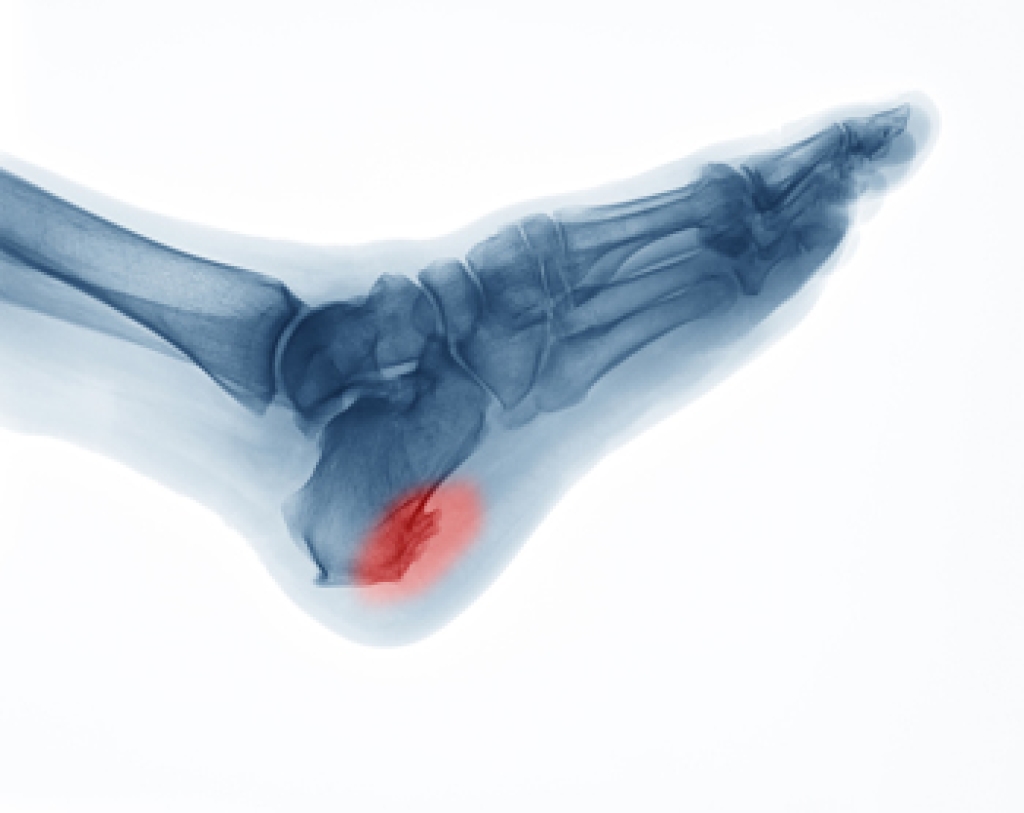

Anterior ankle impingement occurs when bone spurs or inflamed soft tissue at the front of the ankle joint cause pain. It is common during activities that involve dorsiflexion, such as walking uphill, squatting, or playing sports like soccer. These bone spurs, known as osteophytes, often form on the tibia or talus bones as a result of repeated bending or ankle sprains. Common symptoms of anterior ankle impingement include pain with activities that require bending or leaning forward. A podiatrist can use X-rays to detect bone spurs and MRI scans to assess inflammation or scarring. Non-operative treatments focus on wearing shoes with slightly elevated heels, modifying activities, using anti-inflammatory medications, and receiving corticosteroid injections. Strengthening exercises to prevent future problems are also helpful. In cases where conservative measures are ineffective, surgery may be required to remove the bone spurs and restore motion. If the front of your ankle consistently hurts, it is suggested that you schedule an appointment with a podiatrist for an exam, diagnosis and treatment.

Due to the wide variety of potential causes of ankle pain, podiatrists will utilize a number of different methods to properly diagnose ankle pain. This can include asking for personal and family medical histories and of any recent injuries. Further diagnosis may include sensation tests, a physical examination, and potentially x-rays or other imaging tests.